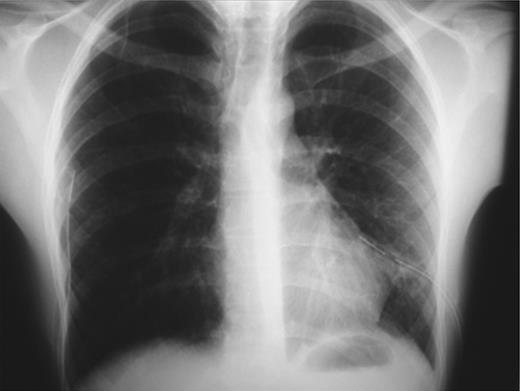

During hospitalization a chest computed tomography (CT) was performed and revealed the presence of blebs at the apices of both upper lungs (Fig. 4). After recovery the patient was referred to a tertiary center for an elective video-assisted thoracoscopic surgery intervention (VATS). Three years after, no recurrence of pneumothorax took place and the patient remains healthy.

CT image showing bilateral blebs on the apices of the upper lobes.